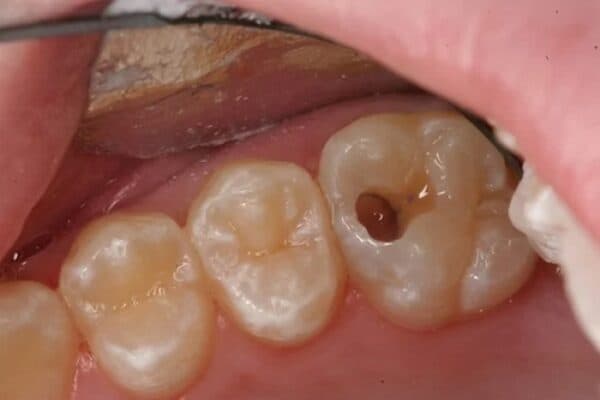

– Sâu răng sâu. Khi sâu răng đã ăn sâu vào lớp ngà răng và tiến gần đến tủy răng, gây ra các cơn đau nhức dữ dội, điều trị tủy răng là cần thiết để ngăn chặn sự tiến triển của bệnh và cứu lấy răng.

Sâu răng thường là nguyên nhân chính dẫn đến phải điều trị tủy.